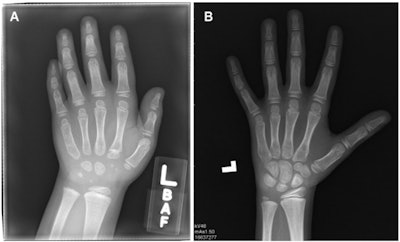

Radiologists can assess skeletal age on hand radiographs faster and more accurately with assistance from an artificial intelligence (AI) algorithm, according to a prospective analysis published online September 28 in Radiology.

After training a deep-learning algorithm using open-source training data from the RSNA Pediatric Bone Age Machine Learning Challenge, the researchers then recruited 93 radiologists at six centers to assess bone age on hand radiographs without AI in 739 cases and with AI in 792 cases.